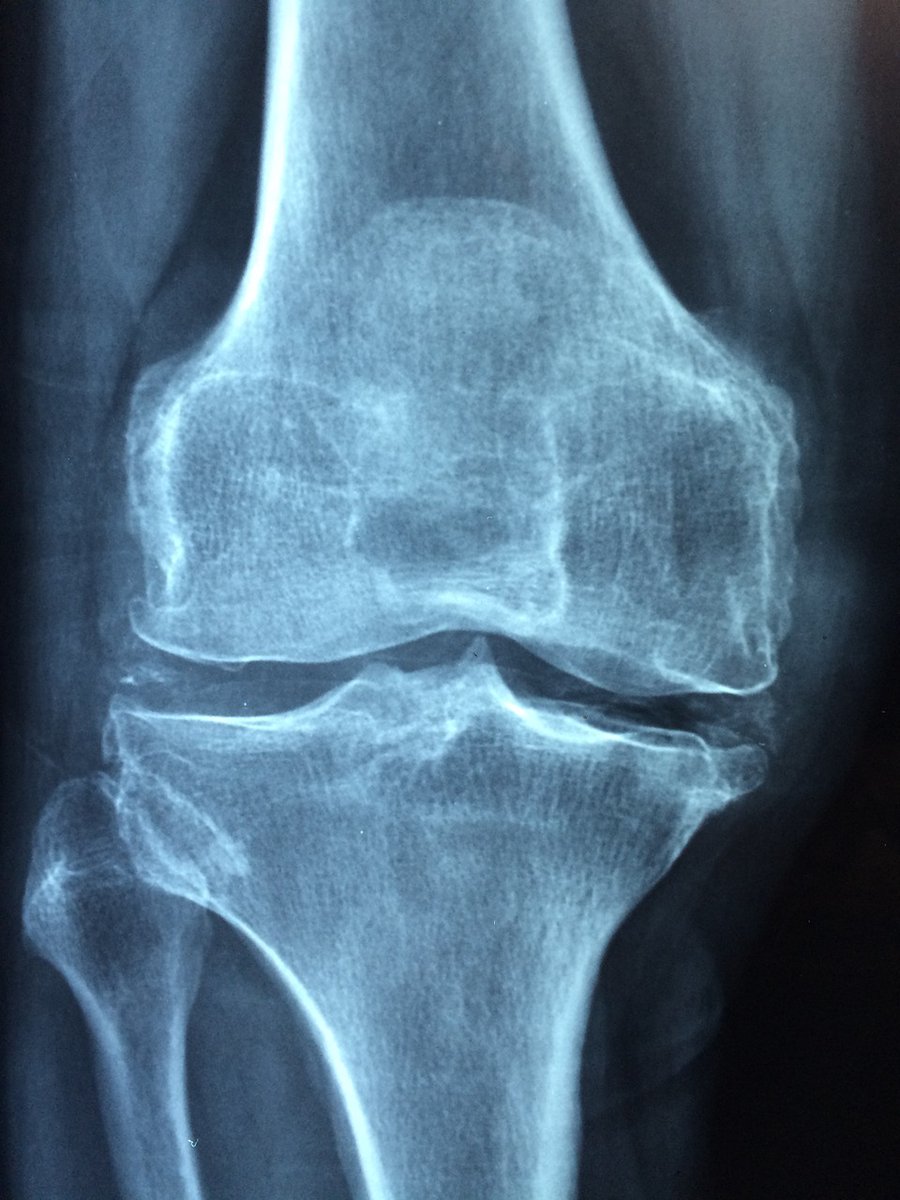

From the professional athlete to weekend warriors we strive in treating each athlete as if it were our own mother! Please visit our website at asmc.md for more information on what injuries we treat. Thank you! #medtwitter #sports #healthcare